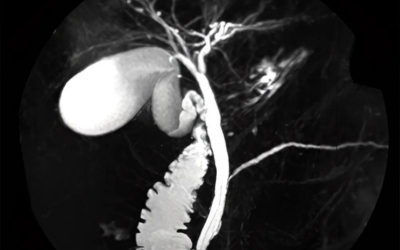

Imaging studies:

Ultrasound, CT scans, and MRIs are vital in spotting tumors and assessing their spread.

ERCP or MRCP:

These procedures evaluate blockages or tumors in the bile ducts.